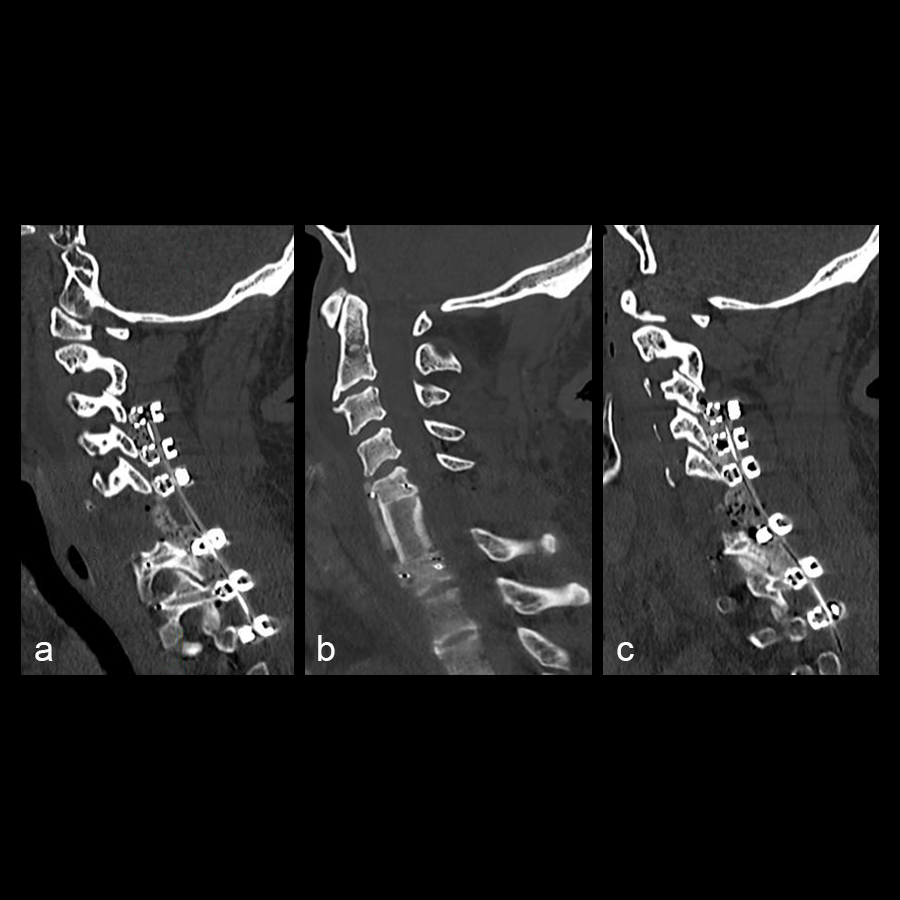

The patient underwent a CT guided biopsy that demonstrated a brachyury positive lesion consistent with a chordoma versus benign notochordal tumor. He underwent a two-stage operation for en bloc resection of the lesion. Cervical spine stabilization was achieved using CMORE® Carbon/PEEK implants. The radiolucent nature of these implants permits artifact-free postoperative imaging and more precise radiation treatment, an important consideration in patients with spinal tumors.

The first stage was a posterior approach with a C3-T3 instrumented fusion using CMORE® Carbon/PEEK lateral mass and pedicle screws (Fig 2) with resection of the posterior elements of C6, mobilization of the C6 and C7 nerve roots and vertebral arteries bilaterally. The second stage was a left sided anterior cervical approach with completion of the C6 spondylectomy and en bloc resection of the C6 lesion. The resected lesion tissue is shown in Fig 3.

The anterior cervical spine was reconstructed from C5-C7 using tricortical iliac crest autograft and an icotec Carbon/PEEK anterior cervical plate system (Fig 4). Following reconstruction, imaging (Fig 5) demonstrated no MRI artifact in the sagittal (a,c) and axial (b,d) planes.